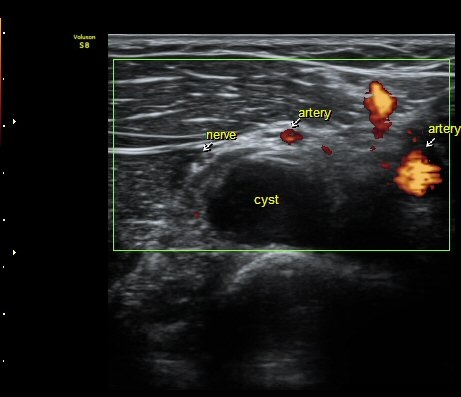

ŽÃËÀÚ¸¦ ¿ä°ñµÎ ºÎÀ§·Î À̵¿ÇÏ´Ï ¿ä°ñµÎ Ç¥Ãþ¿¡ Àú¿¡ÄÚ ³¶Á¾ÀÌ °üÂûµÇ°í ³¶Á¾ÀÇ ¿ÜÃø¿¡¼­

Èİñ°£½Å°æÀÌ ¾Ð¹ÚµÇ°í ÀÖ´Ù(±×¸² 2).

ÀÖ´Ù(±×¸² 6,7). ±×¸² 8. ³¶Á¾°ú Èİñ°£½Å°æ ÁÖÀ§¾Ö¼­ °üÂûµÇ´Â µ¿¸Æ.